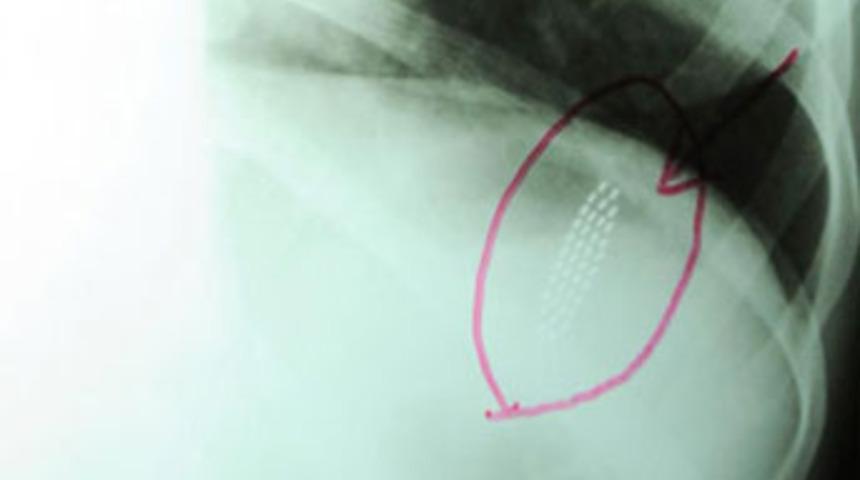

Antalya’da çok yemek yedikten sonra rahatsızlanan midesini boşaltmak isteyen 22 yaşındaki M.B., kusmak için kullandığı 19 santimlik diş fırçasını yuttu. Hastaneye götürülen kızın midesindeki fırça, ’basket’ adı verilen endoskopi malzemesi ile 15 dakikada çıkartıldı.

Aşırı miktarda gıda alan M.B., önceki gece rahatsızlandı. Midesindekileri diş fırçası yardımıyla kusarak boşaltmak isteyen kız, lavabonun karşısına geçti. Öğürmeye çalışırken nefesini kesilen ve boğazının bir yerine kadar gelen diş fırçasını yutan M.B., ailesi tarafından hemen yakındaki Akdeniz Üniversitesi (AÜ) Hastanesi’ne getirildi. M.B.’nin midesindeki 19 santimlik fırça, AÜ İç Hastalıkları Anabilim Dalı Gastroenteroloji Bilim Dalı Uzmanı Dr. Erhan Alkan tarafından ’basket’ adı verilen endoskopi malzemesi ile 15 dakikada çıkartıldı. Sağlığına kavuşan kız, aynı gece taburcu edildi.

M.B.’nin kendisinin nöbetçi olduğu gece hastaneye geldiğini belirten Dr. Erhan Alkan, "Hasta aşırı miktarda yediği gıdaları diş fırçası yardımıyla midesinden kusarak boşaltmak istemiş. Ancak öğürme refleksini uyarmaya çalışırken nefesi kesilmiş ve tekrar derin bir nefes almaya çalışırken boğazının belli bir yerine gelen diş fırçasını yutmuş. Hastanemize geldiğinde midesi o kadar doluydu ki fırçanın baş kısmını tutmak için gıdalardan ayırmak 15 dakika sürdü" diye konuştu.